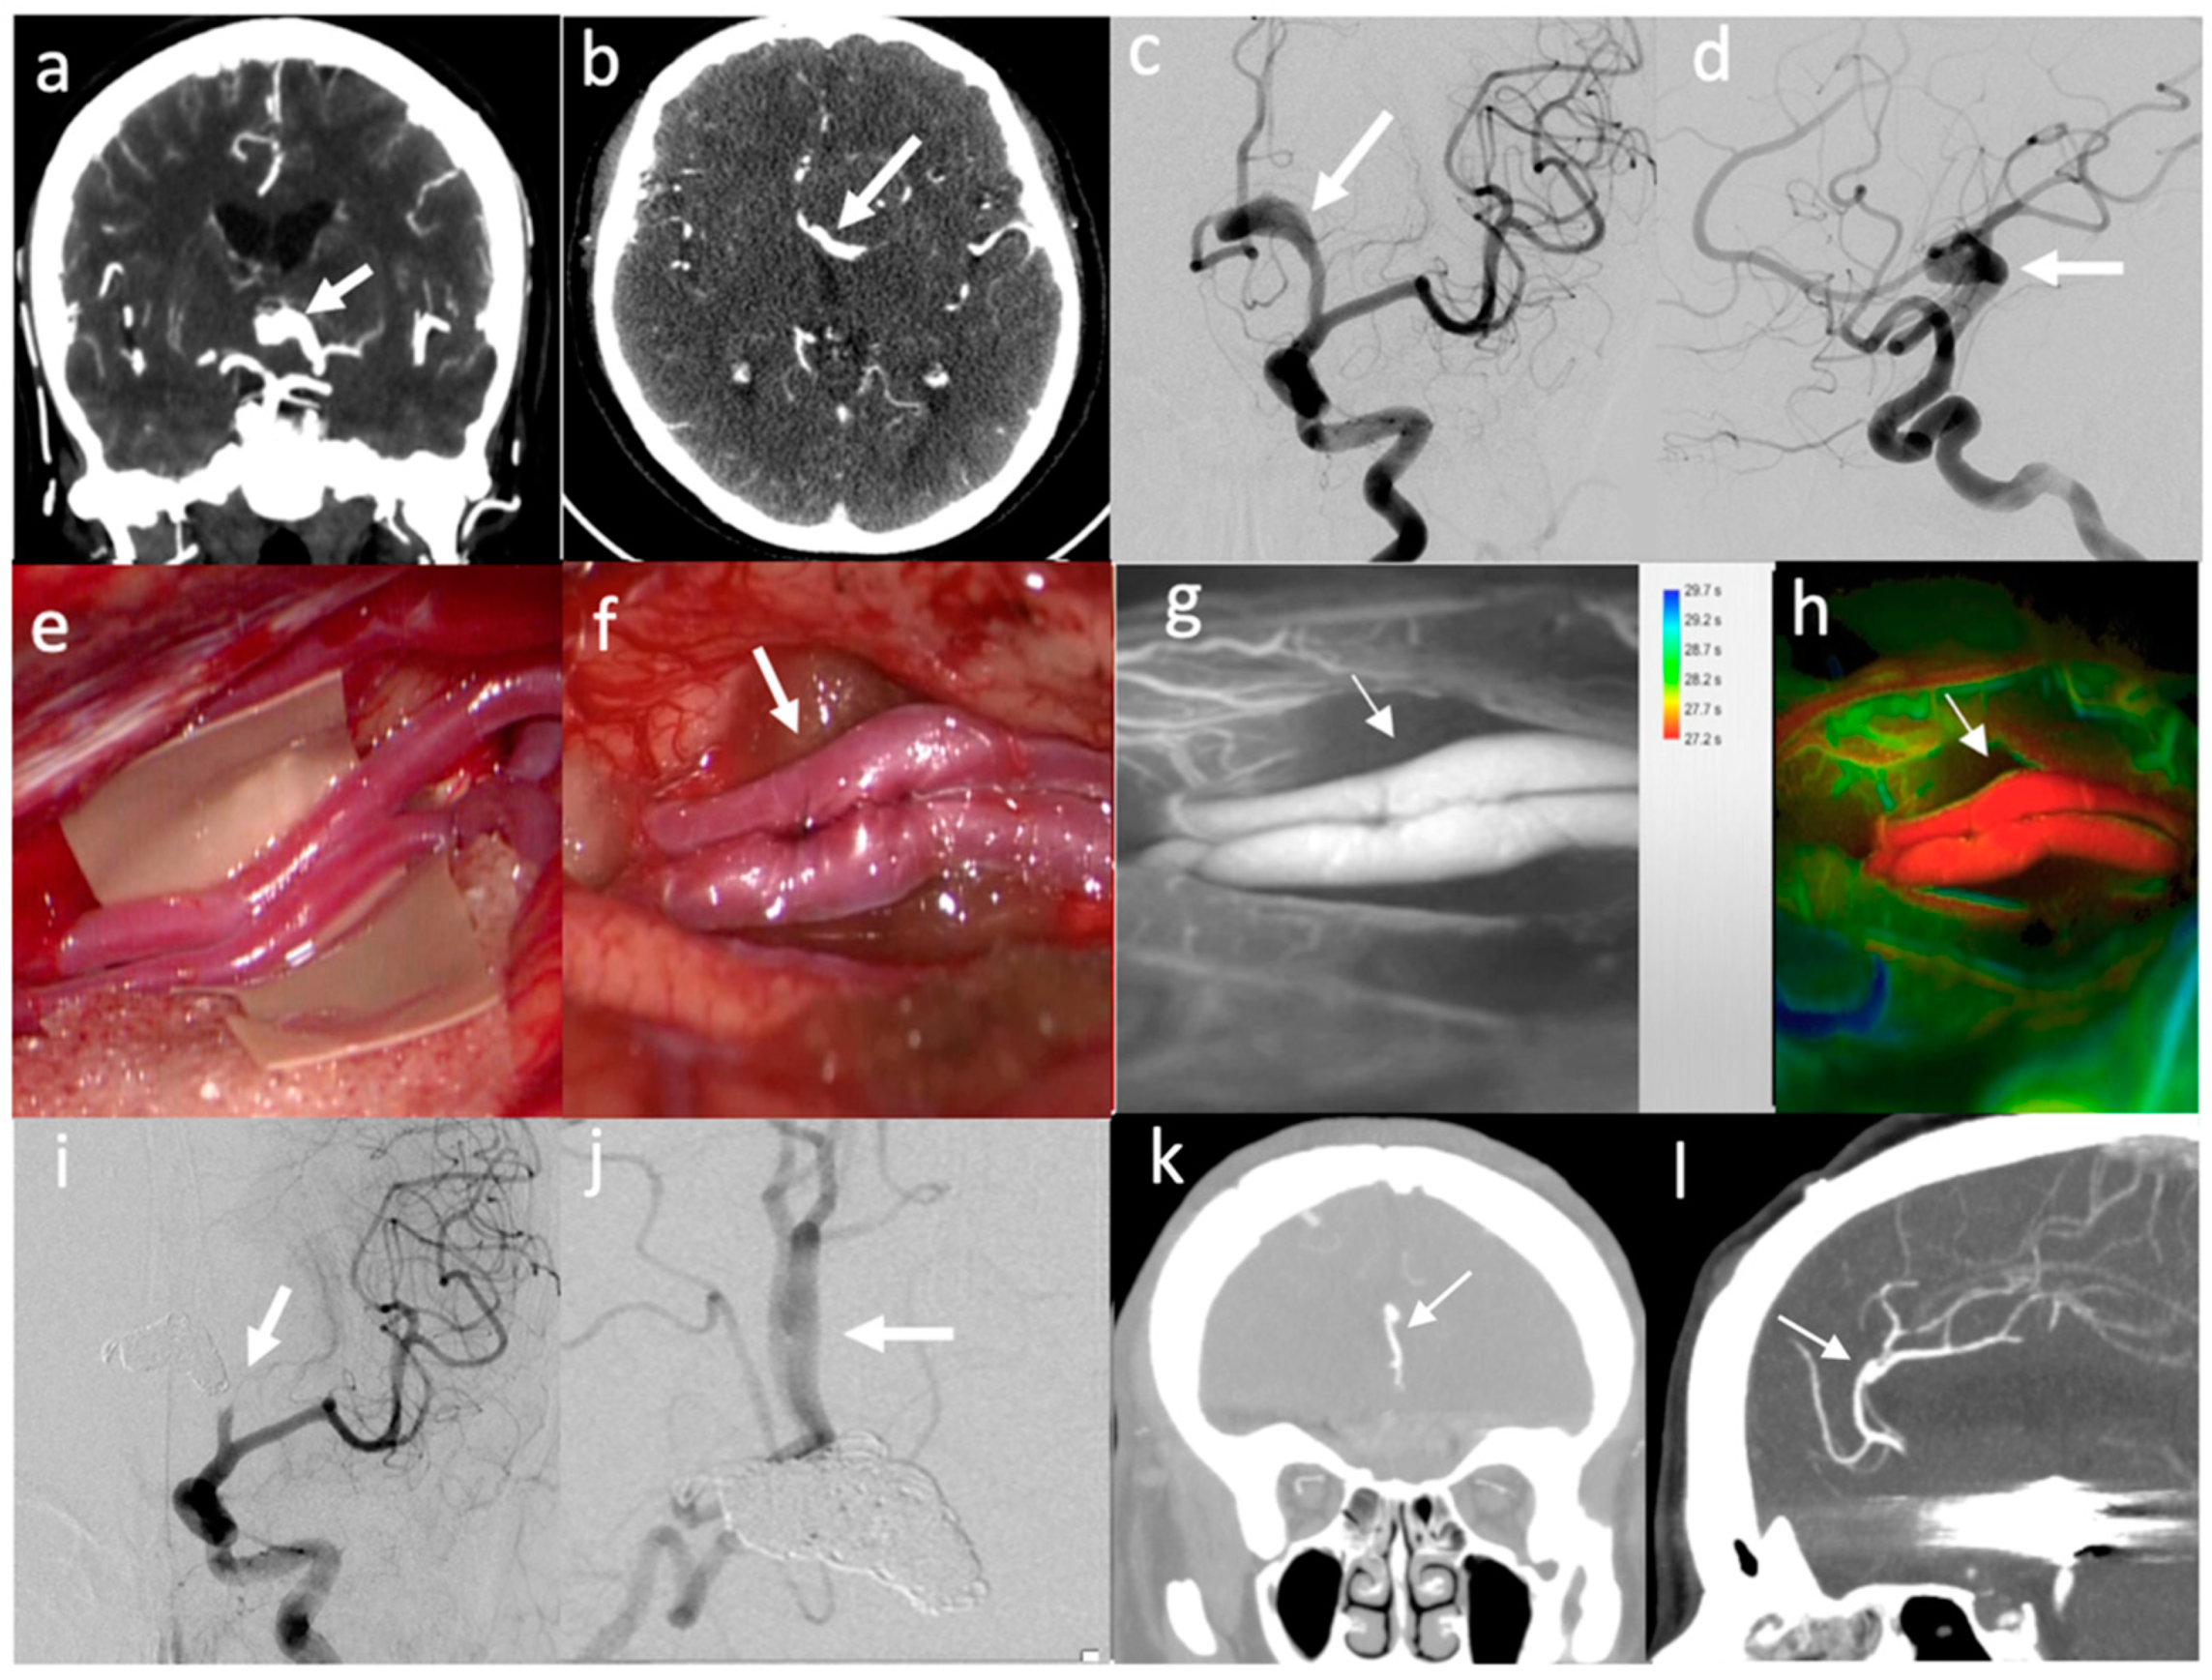

- In three patients, a combined procedure involving multiple bypasses to preserve flow in different territories of the distal ACA was performed. In one case (patient no. 5), a side-to-side perA–perA bypass was performed together with a right STA–CmaA artery bypass using a contralateral STA as a graft, to replace both perA and CmaA territories before endovascularly occluding a complex aneurysm of the proximal right ACA that was already submitted to an unsuccessful endovascular treatment in another institution [24]. In one case (patient no. 11), PerA–PerA and CmaA–CmaA artery bypasses were performed in the same patient to preserve the two distal territories in a complex large aneurysm of the proximal ACA, involving both pericallosal and callosomarginal arteries [20]. In one case (patient no. 23), a similar strategy was planned. However, after intraoperative thrombosis of perA–perA bypass occurred two times, a salvage strategy was considered, by grafting the STA segment at its bifurcation into parietal and frontal branches to create a bridge between the right perA proximal to the thrombus and the two perA distal to the thrombus.